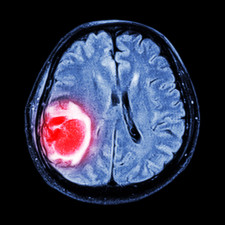

Na rakovinu lymfatických uzlin zemřel v roce 1971 herec Jiří Grossmann. Tehdy ještě nebyla tato choroba léčitelná. Stejné onemocnění překonal Jiří Bartoška. Lymfom se stal osudným pro Karla Gotta. Objevili ho při operaci náhlé příhody břišní. Příznaky jsou různé. Zvětšení uzlin na krku, teploty, které se vracely, pocení.